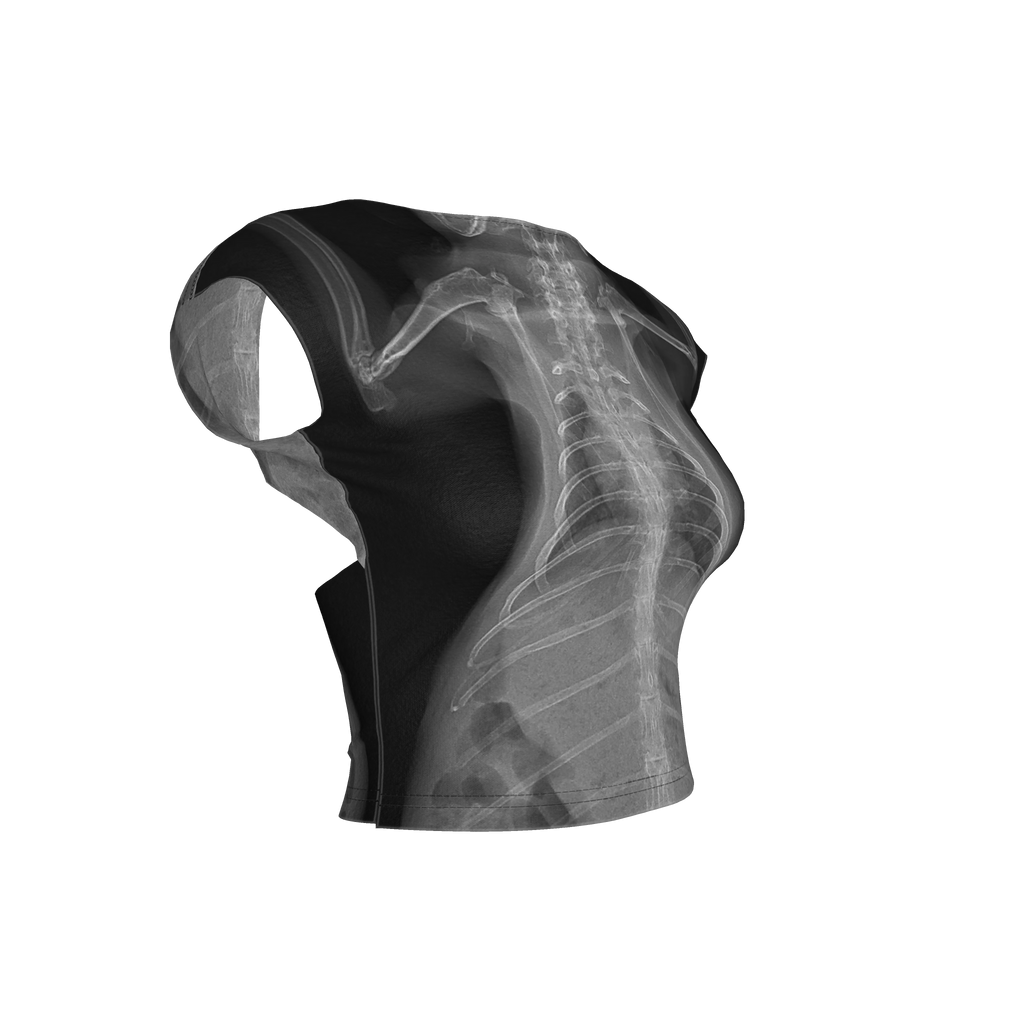

Toll of Love Backless Top

My pet rabbit had a health crisis earlier this year and needed intensive care. It was a long night at the hospital, but she is doing well. Her X-rays were a beautiful thing to come out of a horrible night and I made this outfit to transform those memories into something beautiful.